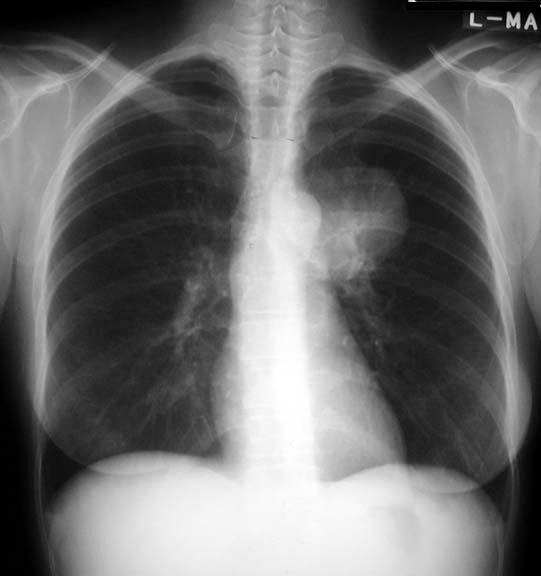

Mass

• Round homogenous density

• Sharp margins

• Medial portion pleural based (acute angle)

This is a case of squamous cell lung cancer.